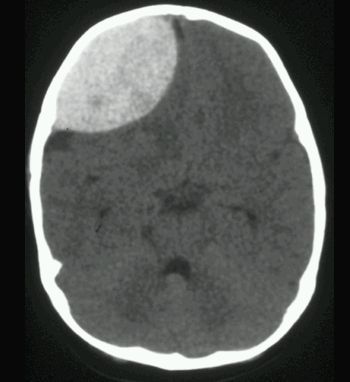

KRWIAK NADTWARDÓWKOWY

TK